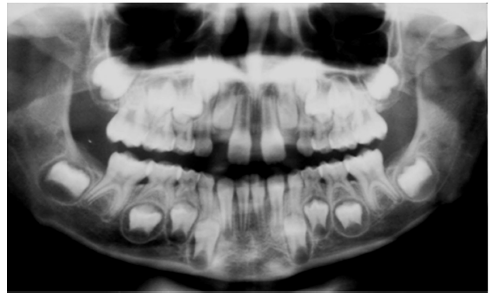

Em relação à imagem, assinale a alternativa que contém a afirmativa CORRETA.

(Fonte: FORMIGA FILHO, A. L. N. Interpretação radiográfica de lesões nos maxilares por alunos de odontologia da UFPB. Trabalho de conclusão de curso. UFPR. João Pessoa, 2009)